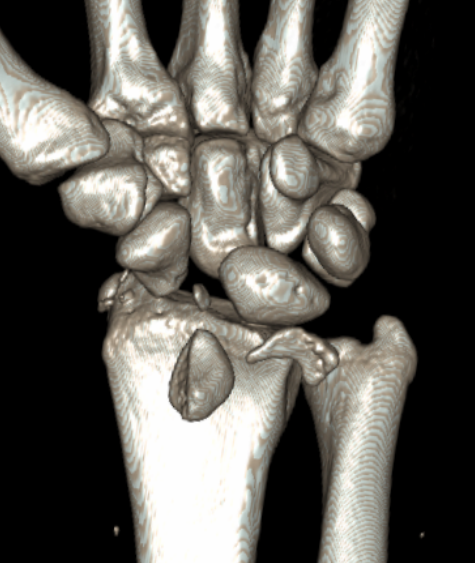

CT

Trans-scaphoid perilunate dislocation

Perilunate dislocation